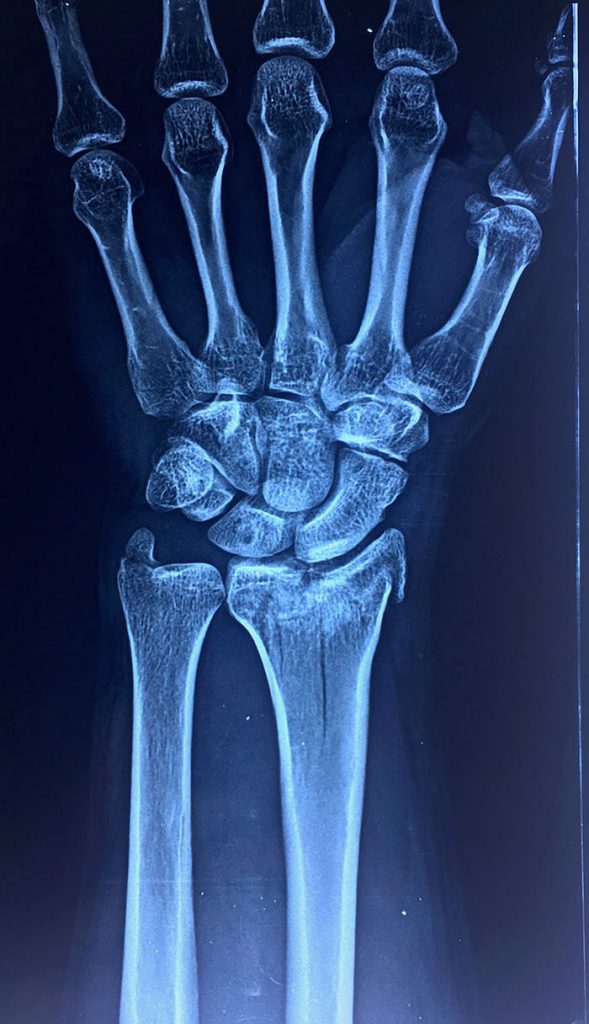

Esta radiografía del momento demostró una fractura tipo impactación de su radio dista en que la superficie articular se perdió completamente con un hundimiento central muy importante, si esto se dejara así el desarrollo de artrosis de esta articulación a corto plazo seria muy importante dejando una muñeca muy dolorosa casi para cualquier actividad, así que nos obliga a realizar una resolución quirúrgica.